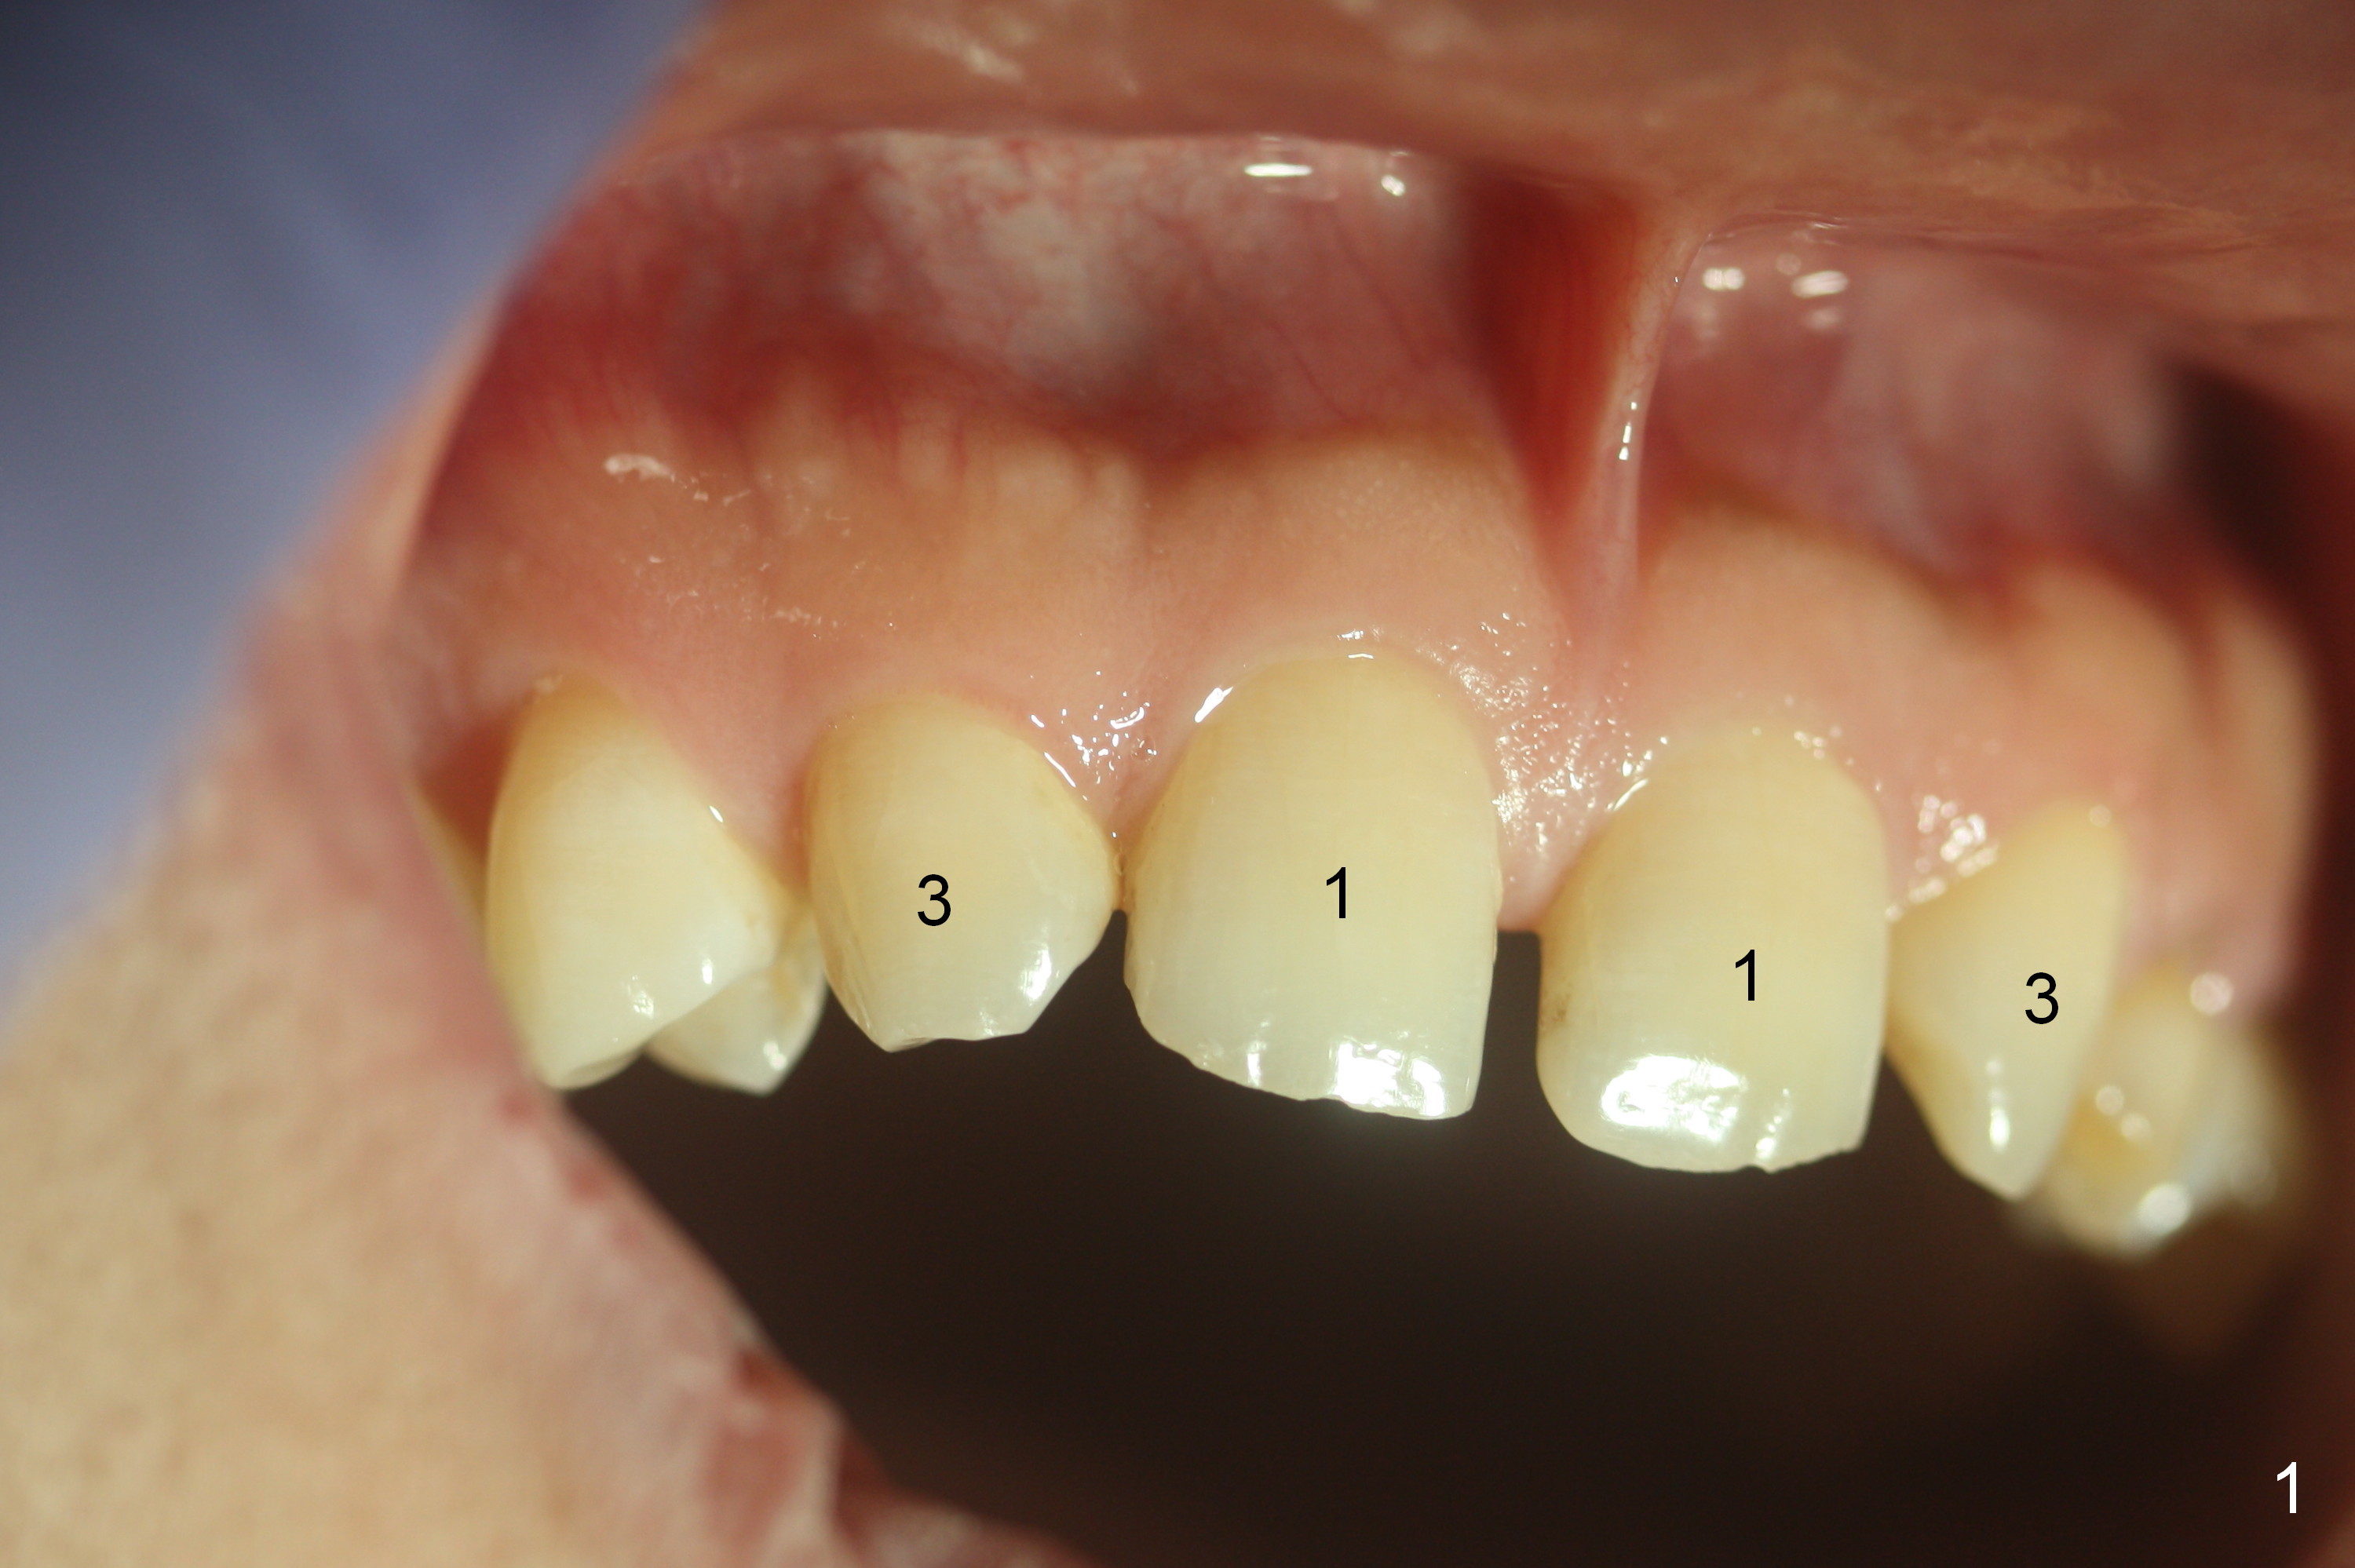

A 38-year-old man has congenitally missing laterals (Fig.1,2) with retention of a deciduous canine (Fig.2,3 C). UL 4 (upper left 1st bicuspid) rotates (Fig.3). LR7 has been extracted (Fig.4).

To improve cosmetics, extract the deciduous tooth (Fig.5), place brackets for the maxillary teeth (6-6), including a lingual button on UL4 to correct the rotation and distalize U3s (Fig.6), close the upper midline diastema and change the midline if needed (Fig.7) and finally place small-diameter implants at U2s (Fig.8 white circles).